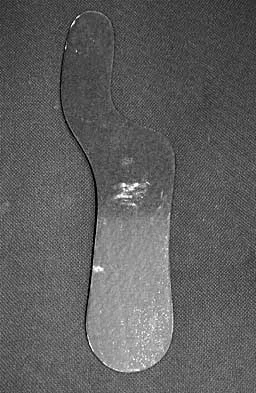

Question 31High Yield

The orthosis shown in Figure 47 is commonly used for